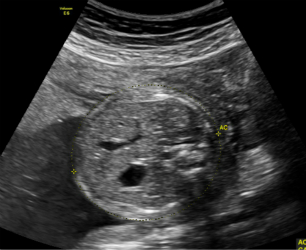

2.妊娠18周~24周超声检查:主要进行胎儿结构畸形的系统筛查。此时期胎儿各器官已发育成熟,系统产前超声检查可记录胎儿各器官结构包括头颅、面部、胸腹腔、心脏、肝脏、双肾、肢体及胎盘等结构,可发现大多数胎儿结构畸形。此阶段是观察胎儿结构和诊断胎儿畸形黄金时段,我们建议所有孕妇在此阶段务必接受一次超声检查。